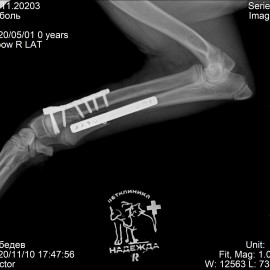

Наш пациент после автотравмы. После осмотра и проведения рентгенологических исследований выл поставлен диагноз - косой диафизарный перелом правой лучевой и локтевой кости со смещением. Была проведена операция - остеосинтез костей правого предплечья.

Снимки после операции.